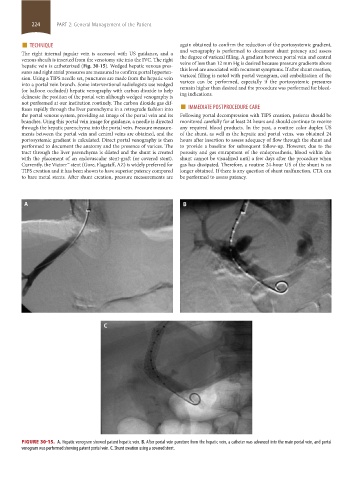

FIGURE 30-15. A. Hepatic venogram showed patent hepatic vein. B. After portal vein puncture from the hepatic vein, a catheter was advanced into the main portal vein, and portal

venogram was performed showing patent portal vein. C. Shunt creation using a covered stent.